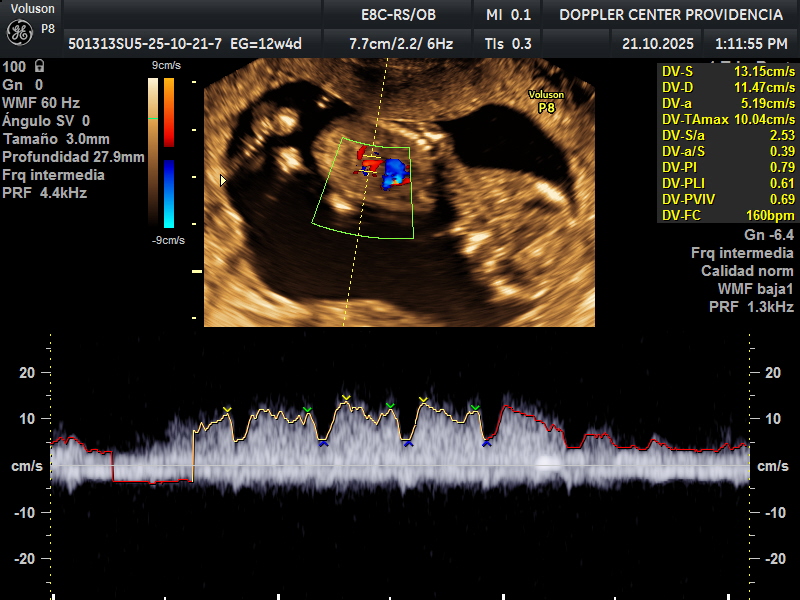

Es una técnica especializada de ultrasonido que utiliza el efecto Doppler para evaluar el flujo sanguíneo en el sistema circulatorio del feto y la madre durante el embarazo.

Se usa principalmente para evaluar el flujo sanguíneo en la placenta, el cordón umbilical y los vasos sanguíneos de la madre y el feto. Esto proporciona información valiosa sobre la salud del embarazo y la circulación fetal.

• Eco Doppler 11-14 semanas